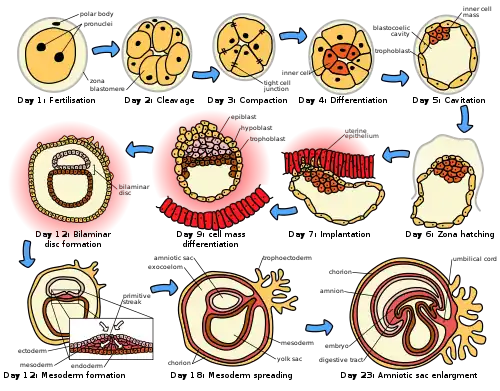

Implantation as one of the early stages of human embryonic development | |

Implantation, also known as nidation[1] is the stage in the embryonic development of mammals in which the blastocyst hatches, attaches, adheres, and invades into the wall of the female's uterus.[2] Implantation is the first stage of gestation, and, when successful, the female is considered to be pregnant.[3] An implanted embryo is detected by the presence of increased levels of human chorionic gonadotropin (hCG) in a pregnancy test.[3] The implanted embryo will receive oxygen and nutrients in order to grow.

In humans, following the stage of hatching that takes place around four to five days after fertilization, the process of implantation begins. By the end of the first week, the blastocyst is superficially attached to the uterine endometrium. By the end of the second week, implantation has completed.[11]

Migration and hatching

There are two stages of migration involved in implantation, the first is the migration of the zygote, and the second is the migration of the trophoblast.[13] Fertilization of the oocyte, takes place in the ampulla of the fallopian tube. Cilia on the lining of the tube move the zygote in its migration towards the uterus.

During this migration the zygote undergoes a number of cell divisions that creates a ball of 16 compacted blastomeres called a morula.[14] The morula enters the uterus after three or four days, and as it does a cavity called the blastocoel is formed in the morula to produce the blastocyst. The blastocyst contains the inner cell mass that will go on to develop into the embryo proper, and an outer cell layer of trophoblasts that will develop into the extraembryonic membranes (fetal membranes).[15]

The blastocyst is still enclosed in the egg-coat known as the zona pellucida, and for it to be able to implant into the uterine wall it must rid itself of this covering. This stage is known as zona hatching, and when there is sufficient dissolution the blastocyst is able to initiate the apposition stage of implantation. Lytic factors in the uterine cavity, as well as factors from the blastocyst itself are essential for the breakdown of the egg-coat. Mechanisms in the latter are indicated by the fact that the zona pellucida remains intact if an unfertilized egg is placed in the uterus under the same conditions.[16]

Apposition

Following zona hatching, the very first loose connection or contact between the blastocyst and the endometrium is called apposition. Apposition is usually made where there is a small crypt in the endometrium, and also where there has been enough breakdown of the zona pellucida to allow the blastocyst trophoblast to directly contact the underlying endometrium. Ultimately, the inner cell mass (also embryoblast), inside the trophoblast layer, is aligned closest to the decidua. If the inner cell mass is not aligned with the decidua at apposition, it has the ability to freely rotate within the trophoblast and achieve this alignment. Apposition is only a weak interaction of the trophectoderm with the uterine epithelium that is unstable to shear stress. Apposition is also reversible allowing repositioning of the blastocyst in the uterus.[14]

Adhesion

Adhesion is a much stronger attachment to the endometrium than the loose apposition.

The trophoblasts adhere by penetrating the endometrium, with protrusions of trophoblast cells.

This adhering activity is by microvilli that are on the trophoblast. The trophoblast have binding fiber connections, laminin, collagen type IV, and integrins that assist in this adhesion process.[19]

Invasion

Invasion is the further establishment of the blastocyst into the endometrium. The protrusions of trophoblast cells that adhere into the endometrium continue to proliferate and penetrate into the endometrium using gelatinases A (MMP-2), and B (MMP-9).[25] Trophoblasts invade the uterus attempting to reach maternal blood supply, for setting up the foundation for fetal blood flow.[26] They also secrete preimplantation factor, a peptide that helps their invasion and placenta formation.[27] As these trophoblasts penetrate, they fuse with their neighbours, terminally differentiating into a multinucleated tissue, a syncytium known as the syncytiotrophoblast. Between this layer and the blastocyst lies the cytotrophoblast.[28][29]

When the syncytiotrophoblast reaches the basal membrane beneath the decidual cells, it dislodges them to further invade into the uterine stroma. Dislodging is accomplished by degrading the cell adhesion molecules (CAMs) that link the decidual cells, and the associated extracellular matrix. Degradation is achieved by the secretion of tumor necrosis factor-alpha from the syncytiotrophoblast, which inhibits the expression of CAMs and beta-catenin. The extracellular matrix is degraded by metalloproteinases such as collagenases, gelatinases and matrix metalloproteinases, and by serine proteases.[30] The collagenases digest Types I, II, III, VII and X collagen.[30] The gelatinases exist in two forms; one digesting Type-IV collagen and one digesting gelatin.[30] The extracellular matrix is degraded by serine endopeptidases and metalloproteinases. The syncytiotrophoblast can then invade into the endometrium taking the embryo with it where it becomes embedded.[30] Eventually, the syncytiotrophoblast comes into contact with maternal blood and forms chorionic villi – the beginning of placentation. Following invasion, the breach in the uterine epithelium made by the blastocyst's entry is sealed by a fibrin plug. The fibrin plug is a coagulation of a blood clot and cellular debris.[11]